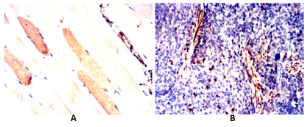

Calponin h1 (CN) is a differentiation marker of smooth muscle cells that has been reported to be down-regulated in the blood vessels of several human tumors.

WB    1/500 - 1/2000

IHC    1/100 - 1/500